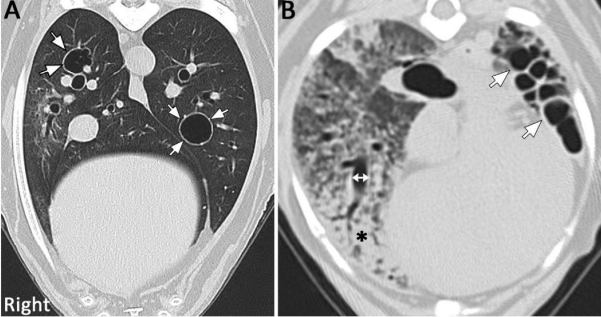

A diminuição da atenuação pulmonar indica redução na opacidade do tecido pulmonar e pode ocorrer devido a excessos anormais de ar (figura 2), como no caso de aprisionamento de ar, ou por diminuições anormais no volume de sangue nos vasos sanguíneos intrapulmonares, como resultado de obstrução vascular ou vasoconstrição devido à baixa perfusão. Apesar de resultarem em áreas com menor opacidade, é mais apropriado categorizá-las como lesões císticas preenchidas com ar, como cistos de paredes finas ou lesões cavitárias, como o enfisema (MASSEAU e REINERO, 2019).

Figura 2: (A) lesões císticas, cheias de ar, caracterizadas por lesões pulmonares bem circunscritas, bem definidas e de paredes finas. (B) padrão de favo de mel, pequenas lesões justapostas, bem definidas, pequenas e cheias de ar.

Fonte: Masseau e Reineroa, 2019

Uma faixa parenquimatosa refere-se a uma opacidade linear espessa e longa que geralmente começa na superfície pleural, atravessando o tecido pulmonar, sem delinear uma estrutura anatômica específica (figura 3). O padrão em favo de mel, indica destruição de tecido, substituição por fibrose e distorção da arquitetura pulmonar. Cistos em favo de mel variam em tamanho (geralmente 3–10 mm), têm paredes bem definidas, devem ser múltiplos (pelo menos 3), cheios de ar e geralmente ocorrem em aglomerados ou fileiras (WEBB et al., 2015).